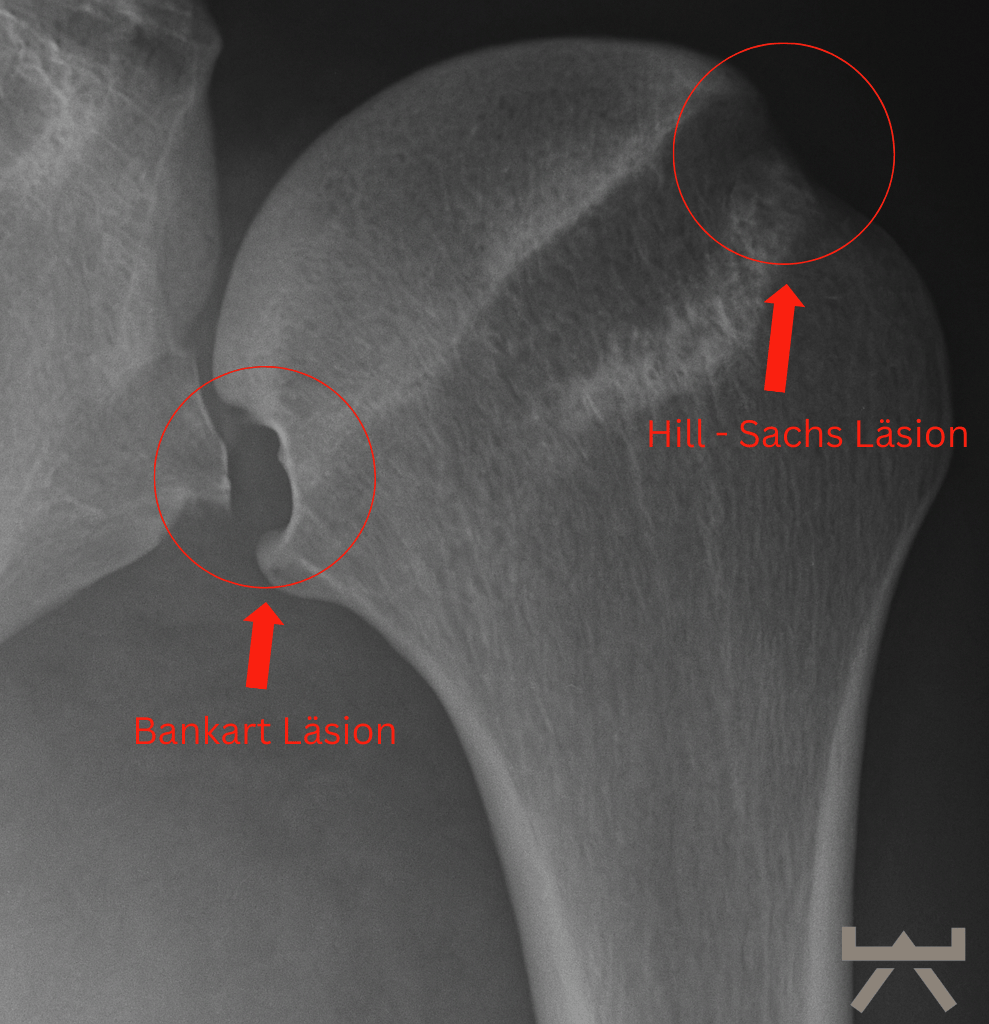

In einigen Fällen können bei einer traumatischen Schulterluxation mehrere Strukturen beschädigt werden. Zunächst kann einmal das Bindegewebe der Kapsel und/oder des Labrums gedehnt werden oder reißen. Zum anderen kann sich eine knöcherne „Bankart-Läsion“ entwickeln, bei der es durch den Aufprall zu einer Fraktur am unteren Ende der Schulterpfanne kommt. Dies geht häufig mit einer „Hill-Sachs-Läsion“ einher, einer Delle in der Schulterkopf selbst. Eine Röntgenaufnahme der Schulter kann dies entweder zeigen oder ausschließen.

Bei einer (traumatischen) Auskuglung ist es wichtig, dass eine Bildgebende Untersuchung durchgeführt wird, um weitere Läsionen und mögliche Brüche auszuschließen.

Je jünger sie sind, desto wahrscheinlich ist es, dass sie eine dauerhafte Instabilität haben werden. 7 Darüber hinaus steigt das Risiko einer dauerhaften Instabilität, wenn es deinen dominanten Arm betrifft und eine knöcherne Bankart-Läsion entdeckt worden ist. Darüber hinaus sind der Grad der Schmerz und Einschränkung in ihrem täglichen Leben und das Ausmaß der Angst und Instabilität, die sie erleben, ein wichtiger Faktor bei der Entscheidung, ob sie sich einer Operation unterziehen wollen oder nicht. 8